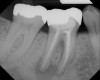

Figure 7  Clinical case of internal root resorption that was treated by orthograde root canal therapy.

Figure 7

Figure 8  Clinical case of internal root resorption that was treated by orthograde root canal therapy.

Figure 8